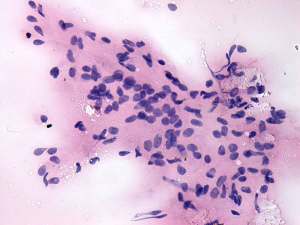

Cytology was performed and resulted in thyroiditis. There were scattered number of lymphocytes and multinucleated giant cells were also found.

The presence of multinucleated giant cells composed of epithelioid cells resembles that observed in de Quervain's thyroiditis. This type of multinucleated cells occurs rarely in autoimmune thyroiditis.